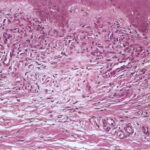

The variable epidermis may be hyperkeratotic with focal parakeratosis, acanthotic to atrophic, and with focal spongiosis. There is proliferation of small blood vessels in the papillary dermis, forming lobular aggregates {glomeruloid proliferation}. The proliferation may be florid, mimicking Kaposi’s sarcoma {acroangiodermatitis} . There is a superficial perivascular lymphocytic infiltrate that surrounds thickened capillaries and venules. The reticular dermis is often fibrotic. Extravasated erythrocytes and hemosiderin are usually present superficially, but they may be identified about the deep vascular plexus as well. Fibrin thrombi may be observed in the small vessels, likely reflecting flow disruption and anoxia. They do not indicate a concurrent coagulopathy. Endothelial necrosis and neutrophils may be present as well, reflecting similar changes, and do not indicate a leukocytoclastic vasculitis